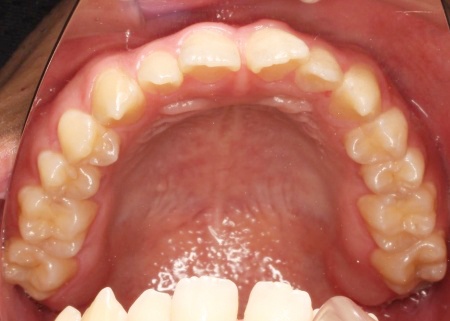

拝見したところ、上下前歯の先端同士が触れ合う「切端咬合(せったんこうごう)」の状態でした。

通常は上前歯が下前歯をわずかに覆うように重なりますが、患者様の場合は上下前歯の先端がほぼ同じ高さで噛み合っているため、受け口のような印象がみられました。

まず、下奥歯(臼歯)を歯茎の外側に持ち上げる「挺出(ていしゅつ)」という処置を行いました。

奥歯が少し高くなることで、下顎全体がわずかに後ろへ動くため、前歯の噛み合わせが整いやすくなります。

加えて、上下の前歯には「IPR」という処置を行いました。これは、歯の表面のエナメル質をごくわずかに削り、歯を動かすためのスペースを作る方法です。

このスペースを利用して前歯を後方へ移動させ、審美性の改善を目指しました。